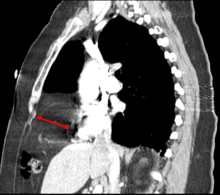

Morgagni hernia

This rare anterior defect of the diaphragm is variably referred to as Morgagni, retrosternal, or parasternal hernia. Accounting for approximately 2% of all CDH cases, it is characterized by herniation through the foramina of Morgagni which are located immediately adjacent and posterior to the xiphoid process of the sternum.[3]